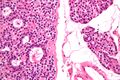

صورة مجهرية لغدوم الجار درقية (يسار) وغدة جارات درقية طبيعية (يمين). صبغة الهيماتوكسيلين واليوزين.

الصور المجهرية